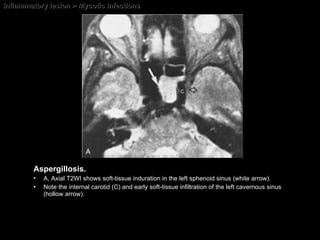

Inflammatory lesion > Mycotic Infections Aspergillosis. A, Axial T2WI shows soft-tissue induration in the left sphenoid sinus (white arrow).  Note the internal carotid (C) and early soft-tissue infiltration of the left cavernous sinus (hollow arrow).